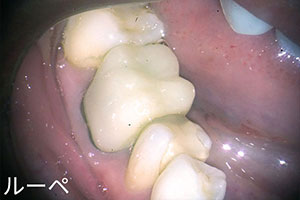

ルーペ(拡大鏡)を使った、精度の高い治療

歯科治療は、実はミリ単位のとても細かい治療です。当院では、そのわずかな違いも見逃さないために、**ライト付きの拡大鏡(ルーペ)**を使用して治療を行っています。

拡大して明るく見ることで、

・削る量を最小限に

・見落としのない、正確な処置

が可能になります。

その結果、歯をできるだけ長く、健康に使っていただくことにつながります。

また、歯科衛生士も同様にライト付き拡大鏡を使用し、虫歯や歯周病の原因となるプラーク(歯垢)を細かい部分までしっかり確認しながら取り除いています。拡大鏡を使うことでお口の中の死角を減らし、より的確で安心できる治療・ケアを行っています。